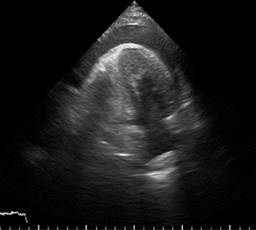

A transthoracic echocardiogram was performed that showed septoapical, apical, inferior apical akinesia, no thinned cardiac segments. Left ventricular ejection fraction (LVEF) 45%, type 1 diastolic dysfunction E/A 0.6, E/e 10, normal dimensions of the right heart chambers with normal right ventricular ejection fraction at rest. Systolic pulmonary artery pressure 26 mmHg, estimated by tricuspid reverse gradient. No pericardial effusion at rest (Figures 1 to 3). The patient evolved to be hemodynamically stable, so a stress echocardiogram was performed to search for viability/residual ischemia on the 6th day after admission to hospitalization. A 5-stage protocol was initiated, starting at 5 μg/kg/min, reaching 20 μg/kg/min. The patient persisted with septoapical and apical akinesia and developed an ischemic response due to developing basal and medial inferior hypokinesia. No changes were recorded in the electrocardiogram at this dose of dobutamine. Esmolol 30 mg intravenous single dose was administered at the beginning of the recovery phase and the study was terminated. In first minutes of recovery, the patient showed sudden deterioration in alertness and pulseless electrical activity. The echocardiogram showed pericardial effusion with a hematic appearance and echocardiographic data of tamponade (Figures 4 to 6). The patient presented cardiorespiratory arrest, so intravenous fluids were administered and an emergency pericardiocentesis was performed, achieving expansion of the right ventricle but with rapid formation of a new pericardial effusion. Later on, he presented asystole which did not revert to basic or advanced cardiovascular resuscitation.

The dobutamine stress echocardiogram is associated with a low rate of complications, with a mortality rate of less than 0.01%, mainly due to ventricular arrhythmias.1 Cardiac rupture has been reported in patients with akinesia or inferior dyskinesia, as result of a recent inferior infarction within 4-12 days. There are reports of cases in which the patient develops sudden chest pain and loss of consciousness accompanied by pulseless electrical activity due to electromechanical dissociation.2-5 In most of the reported cases, the result is fatal. Inotropic stimulation of necrotic and thinned tissue can increase wall stress and result in rupture at the site of least resistance.6 It has been reported of cases where stimulation at low doses (10 μg/kg/min) produces a powerful inotropic stimulation that causes myocardial rupture, observing that the infarction of the inferior wall is more susceptible to rupture.3,4 In this case, the baseline study did not find thinned segments, pericardial effusion or any echocardiographic data compatible with cardiac rupture.7